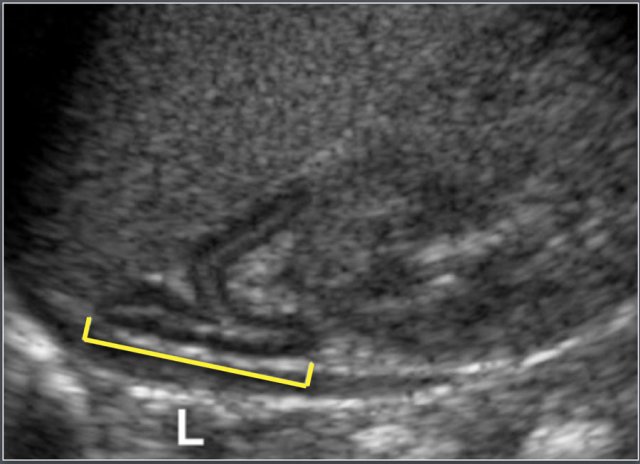

The length (L) of the gland is defined as the maximum cephalocaudal dimension (either coronal or sagital plane).

The width is defined as the maximum thickness of one of the limbs.

Sagittal measurement of the adrenal gland.